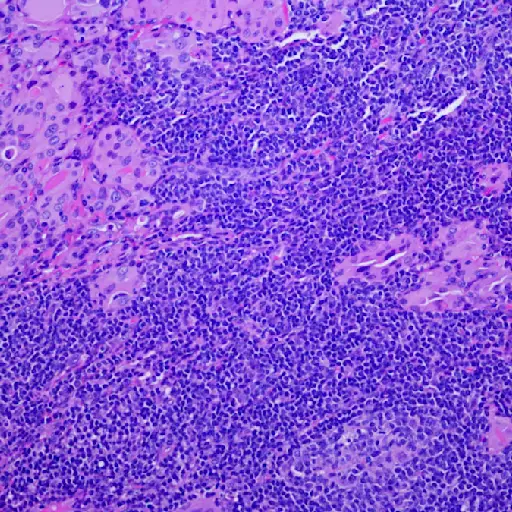

Molar Decay

Molar decay and infections of the sinuses, adenoids, tonsils, genitourinary tract, gall float and kidney can trigger hives, co-ordinate to a written report published in the journal Advances in Dermatology and Allergology. If you lot have chronic hives, it is probably a good idea to see your dentist on a regular basis.